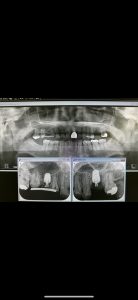

朝より、ソケットリフト

患者さんの希望により左右同時に!

非常に侵襲が少ない術式だからオッケー👌

異物は一切入れないデンサーリフト!

難なく40分で終わり、値も良く6w後には仮歯

印象予定